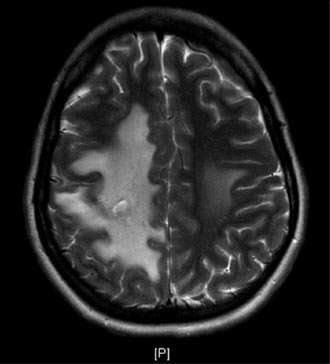

Sinus Thrombosis 2

Figure 2

The blockage can result in brain swelling (edema), stroke, and/or bleeding in the brain (Figure 2).